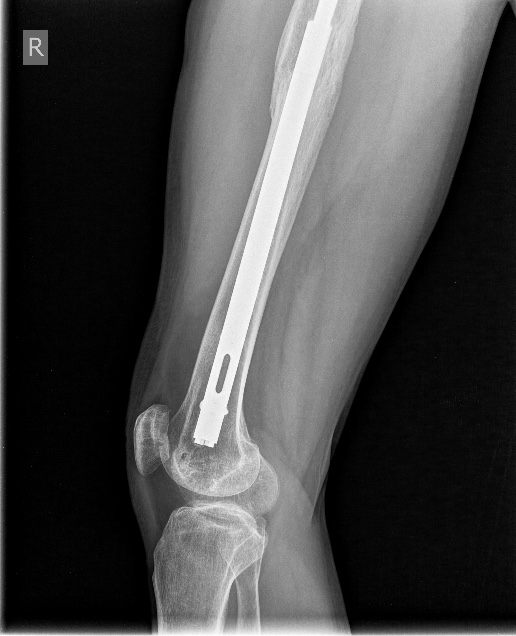

Получается основанием гвоздя вы вошли в дистальный конец стоявшего ранее PFN.

Если так, то будет ли здесь осевая и ротационная стабильность?

Да, конечно. Это по сути посадка на конус.

|

Как только увидел снимок, сразу промелькнула мысль - на старый гвоздь одеть новый ретроградный, именно это первым делом порекомендовал Шнеттлер. Отличные кейсы на этот счёт продемонстрировали Александр Николаевич и Алексей Юрьевич. По-моему, это очень даже reasonable вариант, учитывая аугментацию головки и остеопороз проксимального отдела.